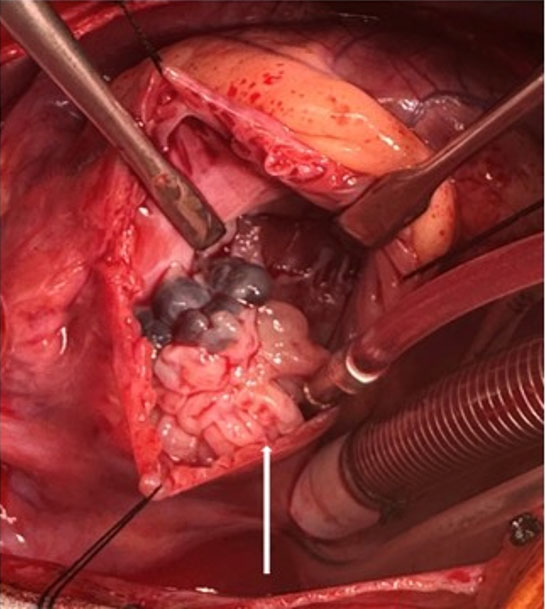

Ultimately resection was recommended for definitive diagnosis and therapy. Intra-operatively, a large 26 × 17 × 15 mm multi-lobular polypoid mass (Figure 3) stemmed from the septal leaflet of the tricuspid valve by the anteroseptal commissure. The valve was reconstructed using autologous pericardium. Post-operative transesophageal echocardiogram showed a well-functioning tricuspid valve. Tissue histopathology identified avascular fibroelastic tissue surrounded by a thin layer of endocardium, consistent with papillary fibroelastoma (PFE). The patient remains asymptomatic at follow-up with a well-functioning tricuspid valve.

Figure 3: Intra-operative imaging of the tricuspid valve mass which appears cystic and nodular on gross inspection (white arrow).